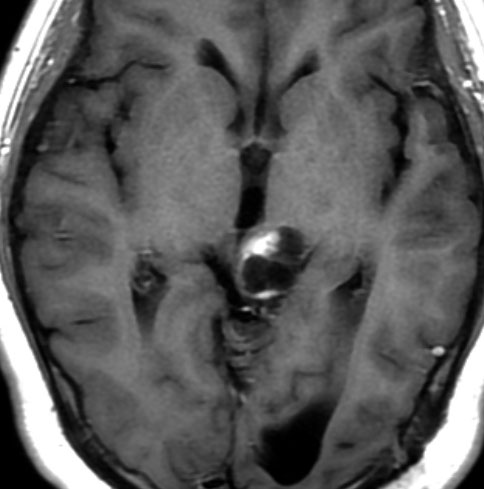

毛様細胞性星細胞腫であり,基本的には初回手術で全摘出できるのですが,現実的には,技術的に難しすぎるので部分摘出で終えることが多いでしょう。この子は,15歳の時に閉塞性水頭症のために,頭痛,嘔吐,意識障害,瞳孔不同となりました。開頭部分摘出術と第3脳室開窓術で回復して,その後にカルボプラチンとビンクリスチンの化学療法を受けました。

でも腫瘍増大が止められずに,発症1年後に54グレイ30分割の放射線治療を受けています。さらにその半年後くらいから再増大しましたが,スードプログレッションと考えられました。上左MRIは放射線治療前,上右MRIは放射線治療1年後です。毛様細胞性星細胞腫は放射線治療後に一過性増大(多くはのう胞性増大)することが多いです。

のう胞性拡大が止まらず,発症3年後にまた再開頭手術 (left occipital transtentorial approach) で亜全摘出しました。右は術後の画像です。初発時の最初の手術で亜全摘出あるいは全摘出 gross total removalできていればと思える例です。